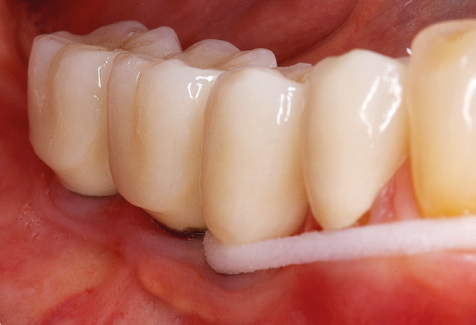

Abb. 4: Für das Sondieren an dentalen Implantaten sind biegsame, millimeterskalierte Sonden empfehlenswert (z.B. Colorvue Kit PCV11KIT6, Hu-Friedy). – Abb. 5a und b: Eine gerade Arbeitsspitze (1P, W&H Dentalwerk Bürmoos GmbH) ist universell für die Instrumentierung natürlicher Zähne geeignet. – Abb. 6: Für die Bearbeitung schwer zugänglicher Bereiche der Zahn- und Wurzeloberflächen (z.B. Furkationen) bieten sich gebogene Arbeitsspitzen (3Pr/3Pl, W&H Dentalwerk Bürmoos GmbH) an. – Abb. 7: Die spitz zulaufende sechseckige Implantatreinigungsspitze (1I, W&H Dentalwerk Bürmoos GmbH) ermöglicht eine atraumatische und effiziente Reinigung der Kronen- und Abutmentoberflächen. – Abb. 8: Für die manuelle Instrumentierung der Implantatoberflächen sind Titan- oder Carbonküretten geeignet.

Unerlässlich für die UPT implantat­ prothetisch versorgter Patienten sind natürlich Arbeitsspitzen für die Reini­gung von Implantatoberflächen. Der Implantatreinigungsaufsatz des hier verwendeten Systems zeichnet sich dabei durch eine spitz zulaufende sechskantige konische Form aus. Dieses Design erlaubt ein leichtes atraumatisches Eindringen in die periimplantäre Tasche und zeigt eine gute Reinigungsleistung (Abb. 7).